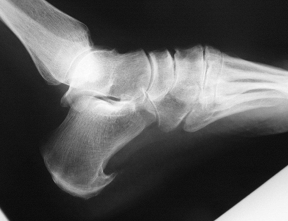

À quoi ressemble une coalition calcanéo-naviculaire?

A